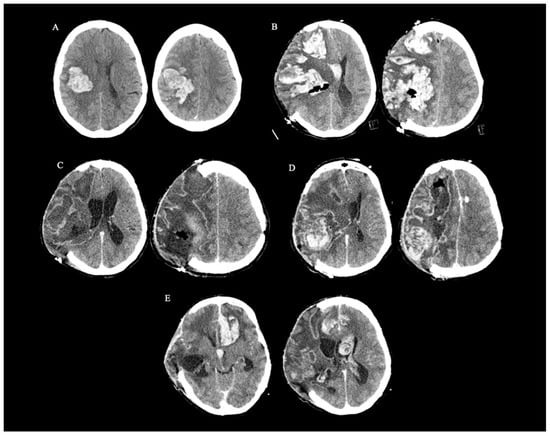

2. Case Report